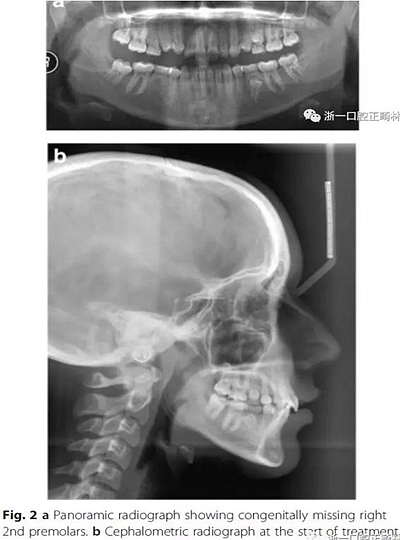

影像學(xué)檢查,右側(cè)第二前磨牙和所有第三磨牙先天性缺失;

頭側(cè)分析,骨性I類關(guān)系,高角型